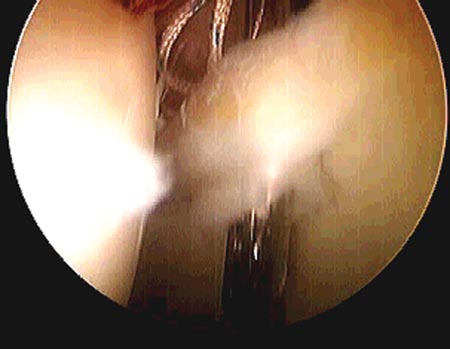

Las lesiones del grupo A consistían en rupturas labrales del tipo radial o fibrilar, no reinsertables a nuestro criterio,por lo que se realiza debridamiento labral. Las lesiones del grupo B, fueron reinsertadas con arpones biodegradables ya que todas eran lesiones del tipo longitudinal, reinsertables a nuestro criterio.

Se utilizaron para la reinserción, arpones biodegradables con sutura simple de alta resistencia. Se colocaron entre uno y tres arpones según la extensión de la lesión.

No se usaron nudos corredizos, debida a la profundidad en la localización de la cadera, y el pasaje de la sutura se hizo por la base de la lesión (Fig. 11 y 12).28,29

Figura 11: Pasaje de la sutura por la base de la lesión./ Figura 12: Reparación estable del labrum.